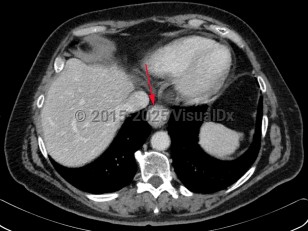

Esophageal carcinoma

Esophageal carcinoma is a malignancy arising from the esophageal mucosa. There are 2 major histologic types: squamous cell carcinoma (SCC) and adenocarcinoma.